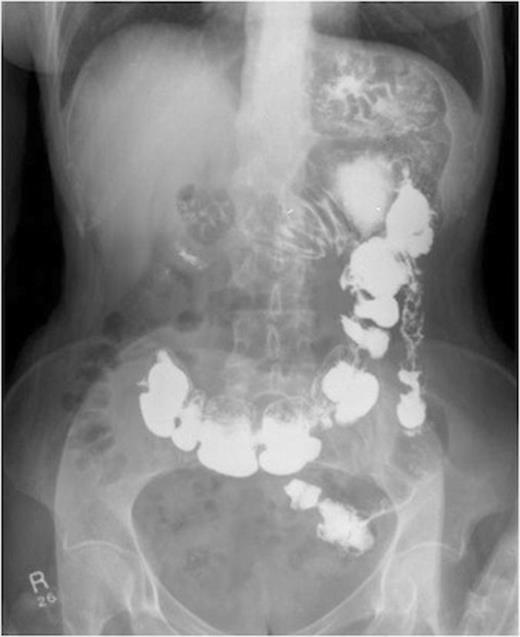

She then had a barium meal and follow through which clearly demonstrated a gastro-colic fistula. This was confirmed by colonoscopy which demonstrated the fistula. There were no signs of neoplasia and the no malignancy was witnessed on biopsy. These findings were confirmed on CT.

A series of radiographs from barium swallow demonstrating gastro-colic fistula

Barium studies are the investigation of choice in diagnosing gastro-colic fistula (1). Thoeny, Hodgson and Scudamore, in the 1960, reported a 95% success rate with barium enema. There have been reports of computer tomography to delineate the fistula and identify underlying pathology (5,6). Gastroscopy and colonoscopy are less sensitive in establishing diagnosis but are important in obtaining multiple biopsies to excluding malignant disease (7).